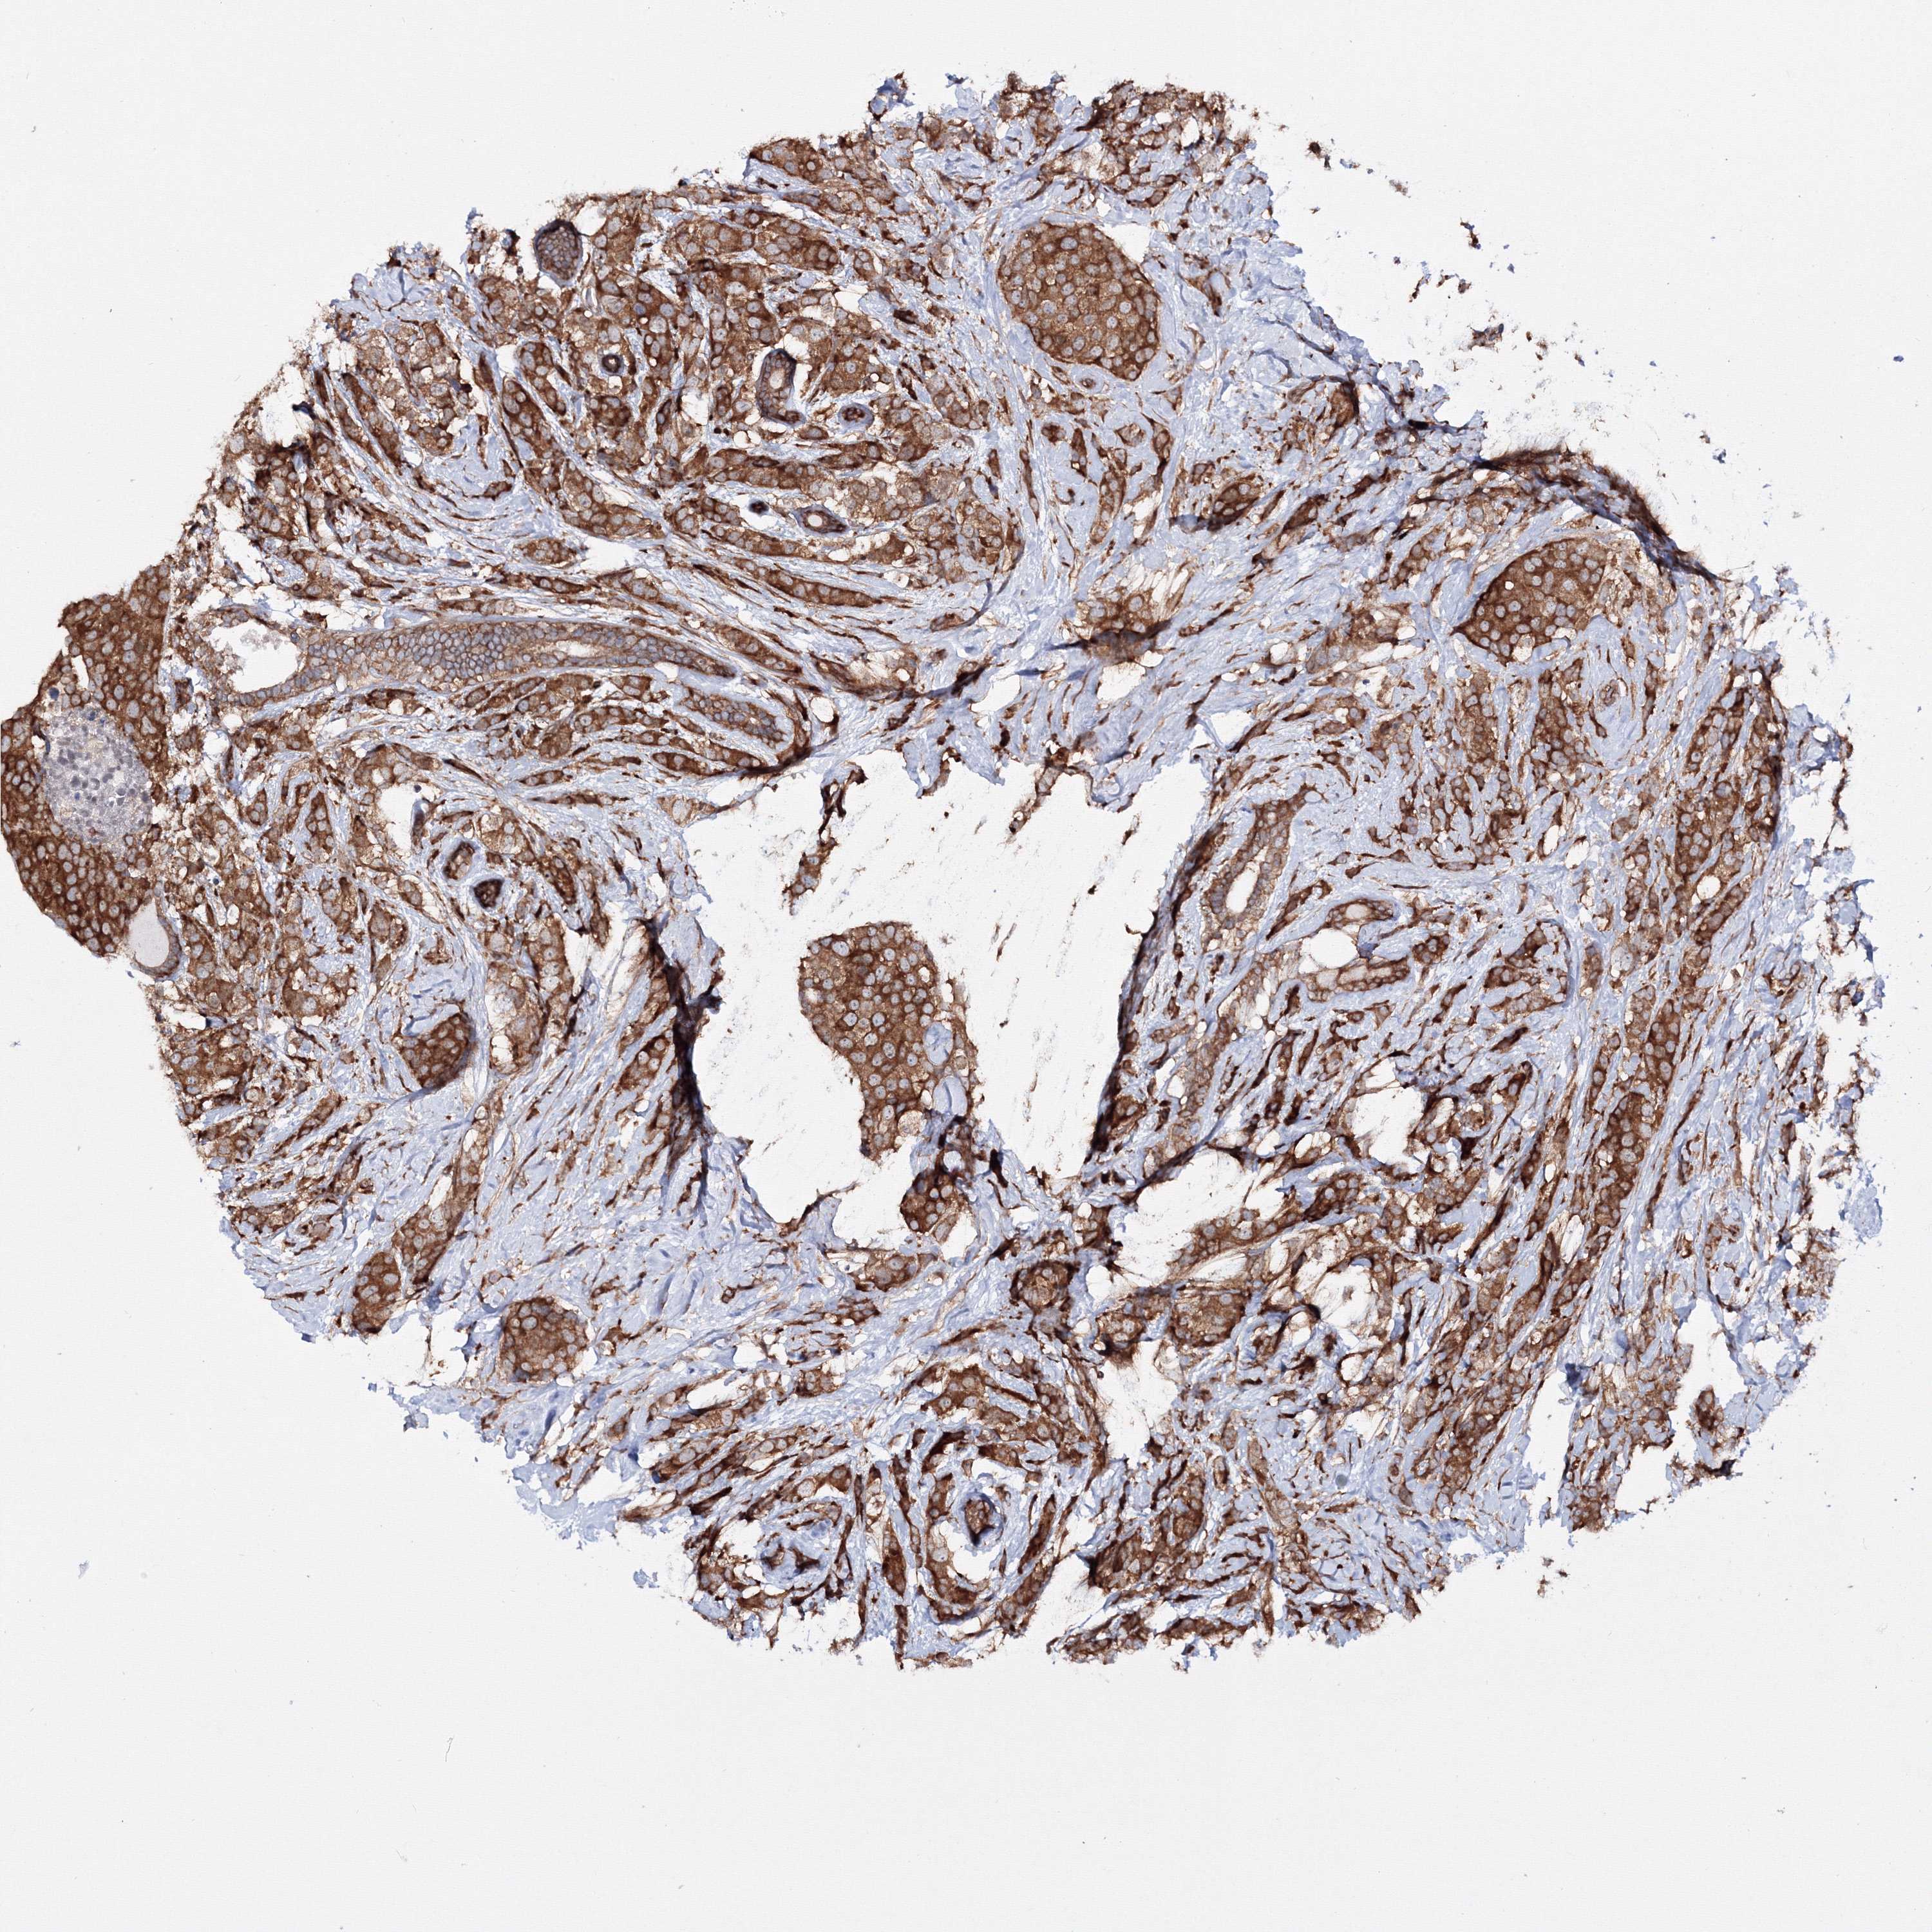

CANCER BREAST CANCER Show tissue menu

BRCA TCGA BRCA VALIDATION PROTEIN EXPRESSION